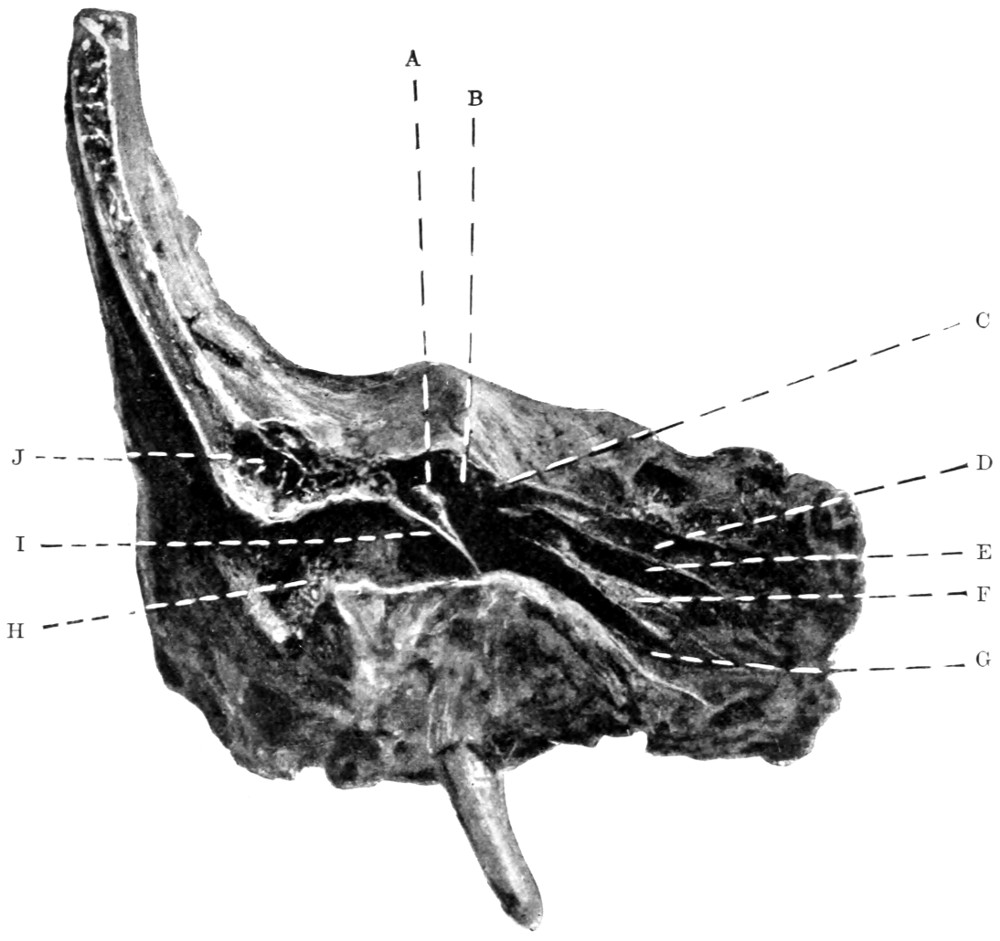

74 A and B. To illustrate the extension of disease from the tympanic cavity and the surgical anatomy of that region (after Hunter Tod) 251

90. To illustrate the operations on the Gasserian ganglion 317

91. To illustrate the operations for exposure of the Gasserian ganglion 321